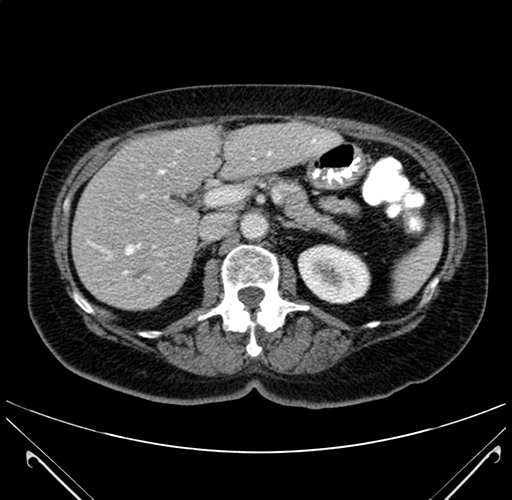

Axial Venous